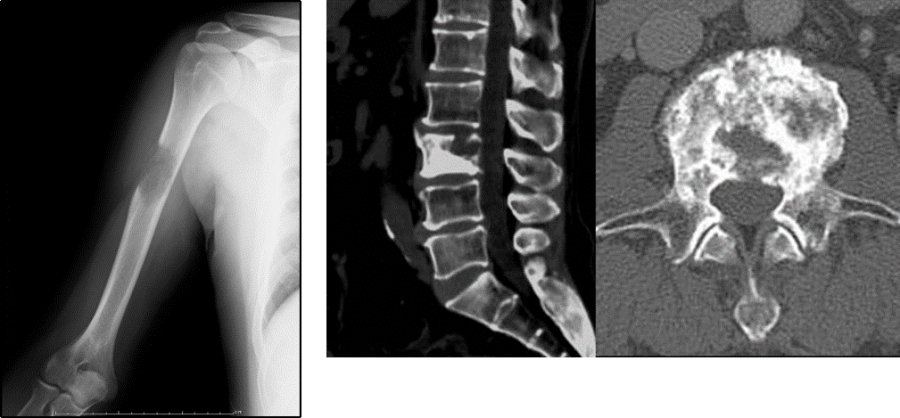

論文の著者は、明細胞RCCは肺、肝臓、または骨に転移または転移する可能性が最も高いと述べています。診断の 5% を占める色素嫌悪性 RCC は、症例のわずか 7% で広がります。

研究者はRCCの転移を引き起こす生体力学の研究を続けていますが、それは特定のパターンに従っているようです。 RCC が広がる可能性のある場所には次のようなものがあります。

• 肺は最も一般的な転移部位であり、症例の 45% を占めます。

• リンパ節

• 肝臓

• 膵臓

• 副腎